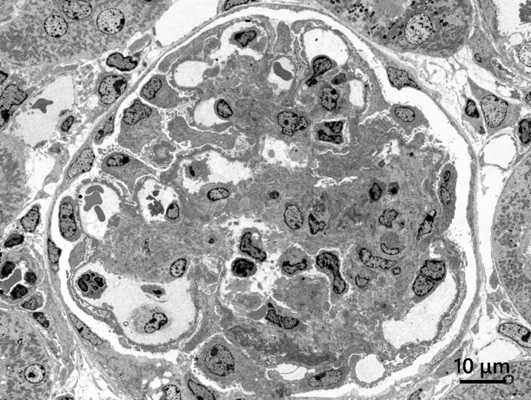

広視野・高コントラスト観察例

試料:ラット腎臓(染色)

加速電圧:80 kV, 観察倍率:x300